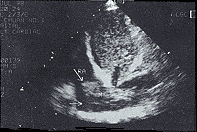

中国超声医学杂志990237 患者,男性,55岁,进行性消瘦,腹胀腹痛一月,加重伴双下肢肿胀一周来诊。体检:慢性消耗病容,精神差,皮肤巩膜黄染,双下肢肿胀,肝肋下4cm,腹部移动性浊音阳性。腹部B超及肝脏CT检查,均诊断为肝硬化合并肝癌、腹水。化验血AFP明显升高。临床诊断肝硬化合并肝癌无疑。患者既往无心脏病史,无双下肢肿胀史及下肢静脉炎。考虑患者近一周来双下肢肿胀尤为明显,且呈进行性加重,有下腔静脉受阻引起双下肢静脉回声障碍的可能,随行双下肢静脉、下腔静脉彩超检查及心脏超声心动图检查。超声结果:双下肢浅深静脉内径明显增宽,壁光滑,腔内未见异常回声。下腔静脉内径增宽,剑突下纵切,显示下腔静脉长轴及入右房切面,下腔静脉离右房入口4cm处,腔内见一不规则腊肠样不均匀中等实质性回声,不活动,与下腔静脉后壁关系紧密,长约7cm,最厚处约3cm,向上方伸入右房腔内(图1),呼吸时下腔静脉内径无变化。心尖四腔心切面,该肿物占右房容积的3/4(图2),右房轻度扩大。彩色多普勒:双下肢静脉、下腔静脉远端血流缓慢,入右房处下腔静脉内血流呈一条窄细的蓝彩血流束经下腔静脉前壁与该占位间的缝隙流入右房,三尖瓣口见少量返流。彩超诊断:右房、下腔静脉内巨大癌栓(肝癌转移)。因属肝癌晚期,行手术取栓已无意义,患者放弃治疗出院。

下腔静脉右房内巨大癌栓(箭头所示)

图1 下腔静脉长轴入右房切面